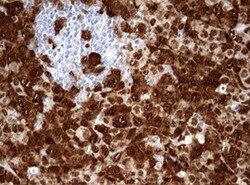

- Immunohistochemical staining of paraffin-embedded human non-small cell lung cancer sample with ALK translocation detected by FISH using anti-ALK mouse monoclonal antibody. (TA801287, 1:50; heat-induced epitope retrieval by 1mM EDTA in 10mM Tris, pH8.0, 120°C for 3min)